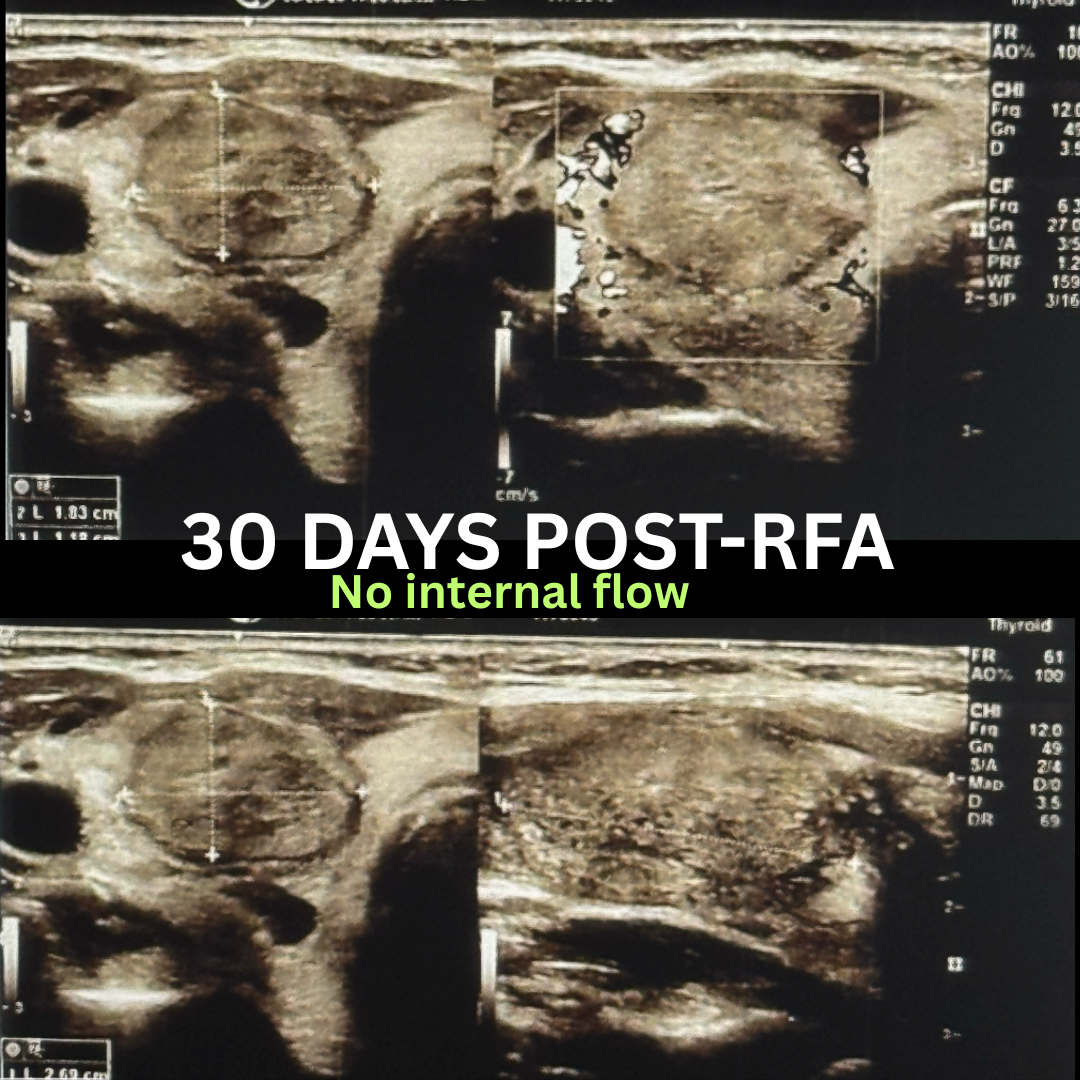

When she learned about Radiofrequency Ablation (RFA), she was uncertain if she would qualify because of the size of her nodule. After reassurance that Dr. Higgins had successfully treated larger nodules with RFA, she decided to proceed. Just one month after her treatment, the nodule had already shrunk by 65%, from 4.1 cm to 2.6 cm.

“At my follow up, everyone was really excited to see the results. We had been waiting a month, and we were all super happy to see it went down 65%.”